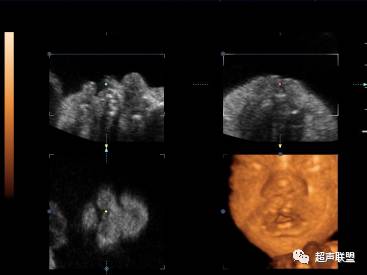

面部

面部的系统性检查

在正中矢状切面获取3维容积

用多平面模式,表面成像观察面部的异常

唇:冠状切面和横切面

:在正中横切面获取3维容积

反转面部切面

在额状面(正面)检查胎儿的唇部和牙槽

在纵轴上胎儿面部旋转180°(反转面部技术),用表面成像模式检查胎儿的继发腭

也可改变显示图标选择由“从前观察”至“从后观察”